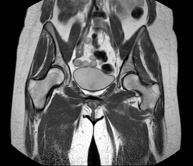

- Hip MRI

Examination for the study of injuries to tendons, muscles and hip joints. Enables early detection of hip osteoarthritis. It is very useful for detecting bursitis and dynamic osteopathy of the pubis, which is common in athletes. It lasts approximately 20 minutes. It is a radiation-free procedure.

- Sacroiliac MRI

Study specifically designed to assess these joints and their inflammation in patients suffering from ankylosing spondylitis. It is also useful in patients with trauma and possible fractures of the sacrum and coccyx. It lasts approximately 16 minutes. It is a radiation-free procedure.